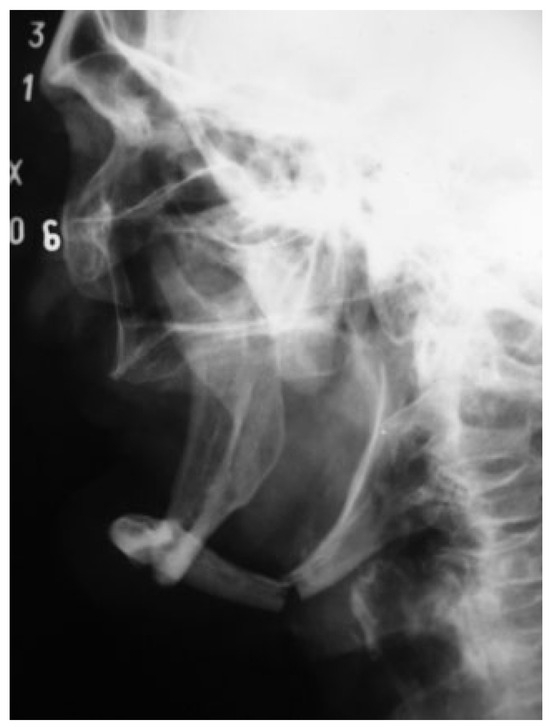

A 72-year-old man was referred to the University Hospital in June 2004 as a fall victim. After extraoral exam, mandibular X-rays showed two fractures at the left mandibular body, one in the left subcondylar region with minimal displacement and one at the right mandibular body (Figure 1 and Figure 2). The patient presented mouthopening limitation, and besides the painful symptomatology during palpation, the patient reported dysphagia and paresthesia of the mental nerve bilaterally and stated that he did not wear dental prosthesis.

Figure 2. Preoperative lateral oblique mandibular radiograph.